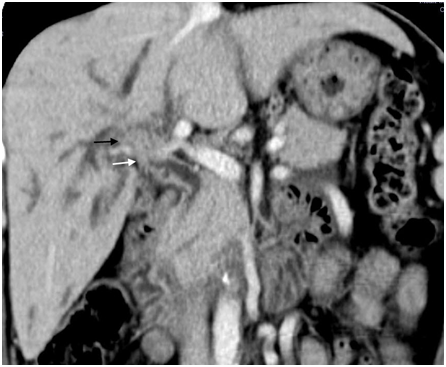

Figure 4 Type IIIb intraductal-growing hilar cholangiocarcinoma – Expansion of common (white arrow) and left hepatic duct (black arrow) due to lobulated intraductal growing tumor is well seen on coronal CT image.